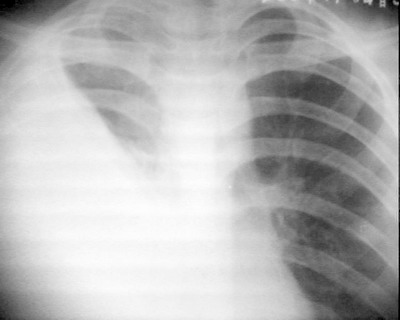

患者/男/17y/因右侧胸痛,发热不退来院拍了个平片!片子质量不好主老师们给个意见吧!谢谢你们!

右侧膈角清晰可见! 左侧肺未见明显异常!请大家给个意见吧!我想给他做个ct! 是不是以先抗炎治一个啊???

右侧胸腔大量积液伴胸膜肥厚,建议ct检查

右胸第1前肋间以下肺野密度均匀一致性增高,内上缘清晰,右隔面/肋隔角消失,其内可见肋骨影,肋间隙无明显改变,胸廓无塌陷,纵隔/气管无移位,考虑右侧大量包裹性积液。

右侧中下野及外带大片状具外内低弧形边缘的致密影,气管,纵隔向左侧偏移,是一个典型的右侧大量胸腔积液!!!应该考虑为结核性的,治疗是先控制症状,然后抽液并服用抗结核药物。

右侧胸腔大量积液伴胸膜肥厚[胸腔积液量大,气管稍左移,心脏无明显移位]。

右大量胸腔积液,这么多胸水,且纵隔及心影移位不明显,为什么没有考虑有肺不张呢,请各战批评指正。

右侧胸腔大量积液伴肺中下叶不张及右肺上叶膨胀不全,性质待查,请结合临床或进一步检查.

纵隔未见明显移位,右侧肺野大片密度增高影,右心缘、右肋膈角及膈面显示不清,考虑胸腔积液伴肺不张情况,建议ct看一下是不是支气管结核。

右侧胸腔积液,包裹形成,伴肺不张,病人年青,考虑结核性胸膜炎可能性大